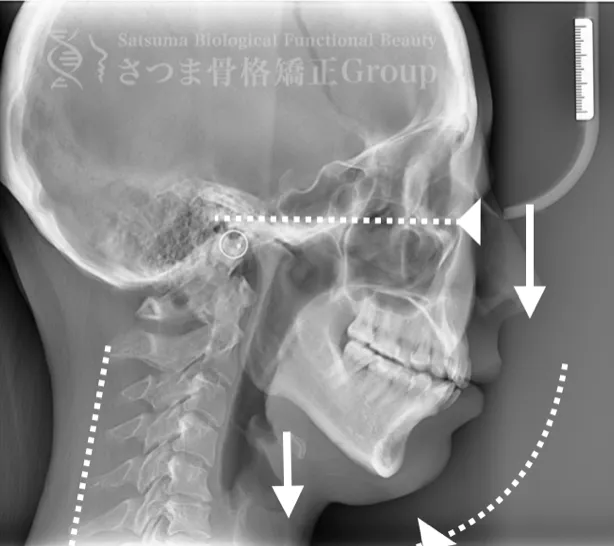

20代女性 S様 初回効果

BEFORE

下顎の後方回転あり

中顔面が伸びて下方に落ちる

中顔面の奥行きを失っている

頚椎ストレートネック

Posterior rotation of the mandible, elongated and downward-dropped midface, loss of midface depth, and cervical spine straightening (straight neck).

AFTER

咬筋と上部頸椎をリリースさせ、顎の前方回転。

さつま式で中顔面の奥行きを作り、短縮。頸部の前湾角の強化。

Release the masseter and upper cervical spine to achieve forward rotation of the jaw.

Using the Satsuma method, create depth in the midface and shorten it.

Enhance the cervical lordosis angle.